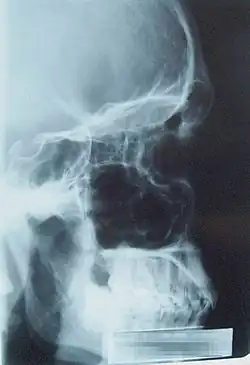

| Lateral view paranasal sinus |

Clinical examination is used to make the diagnosis, and radiography (plain film or CT) is used to confirm it when the characteristic sinus enlargement is observed.[3]